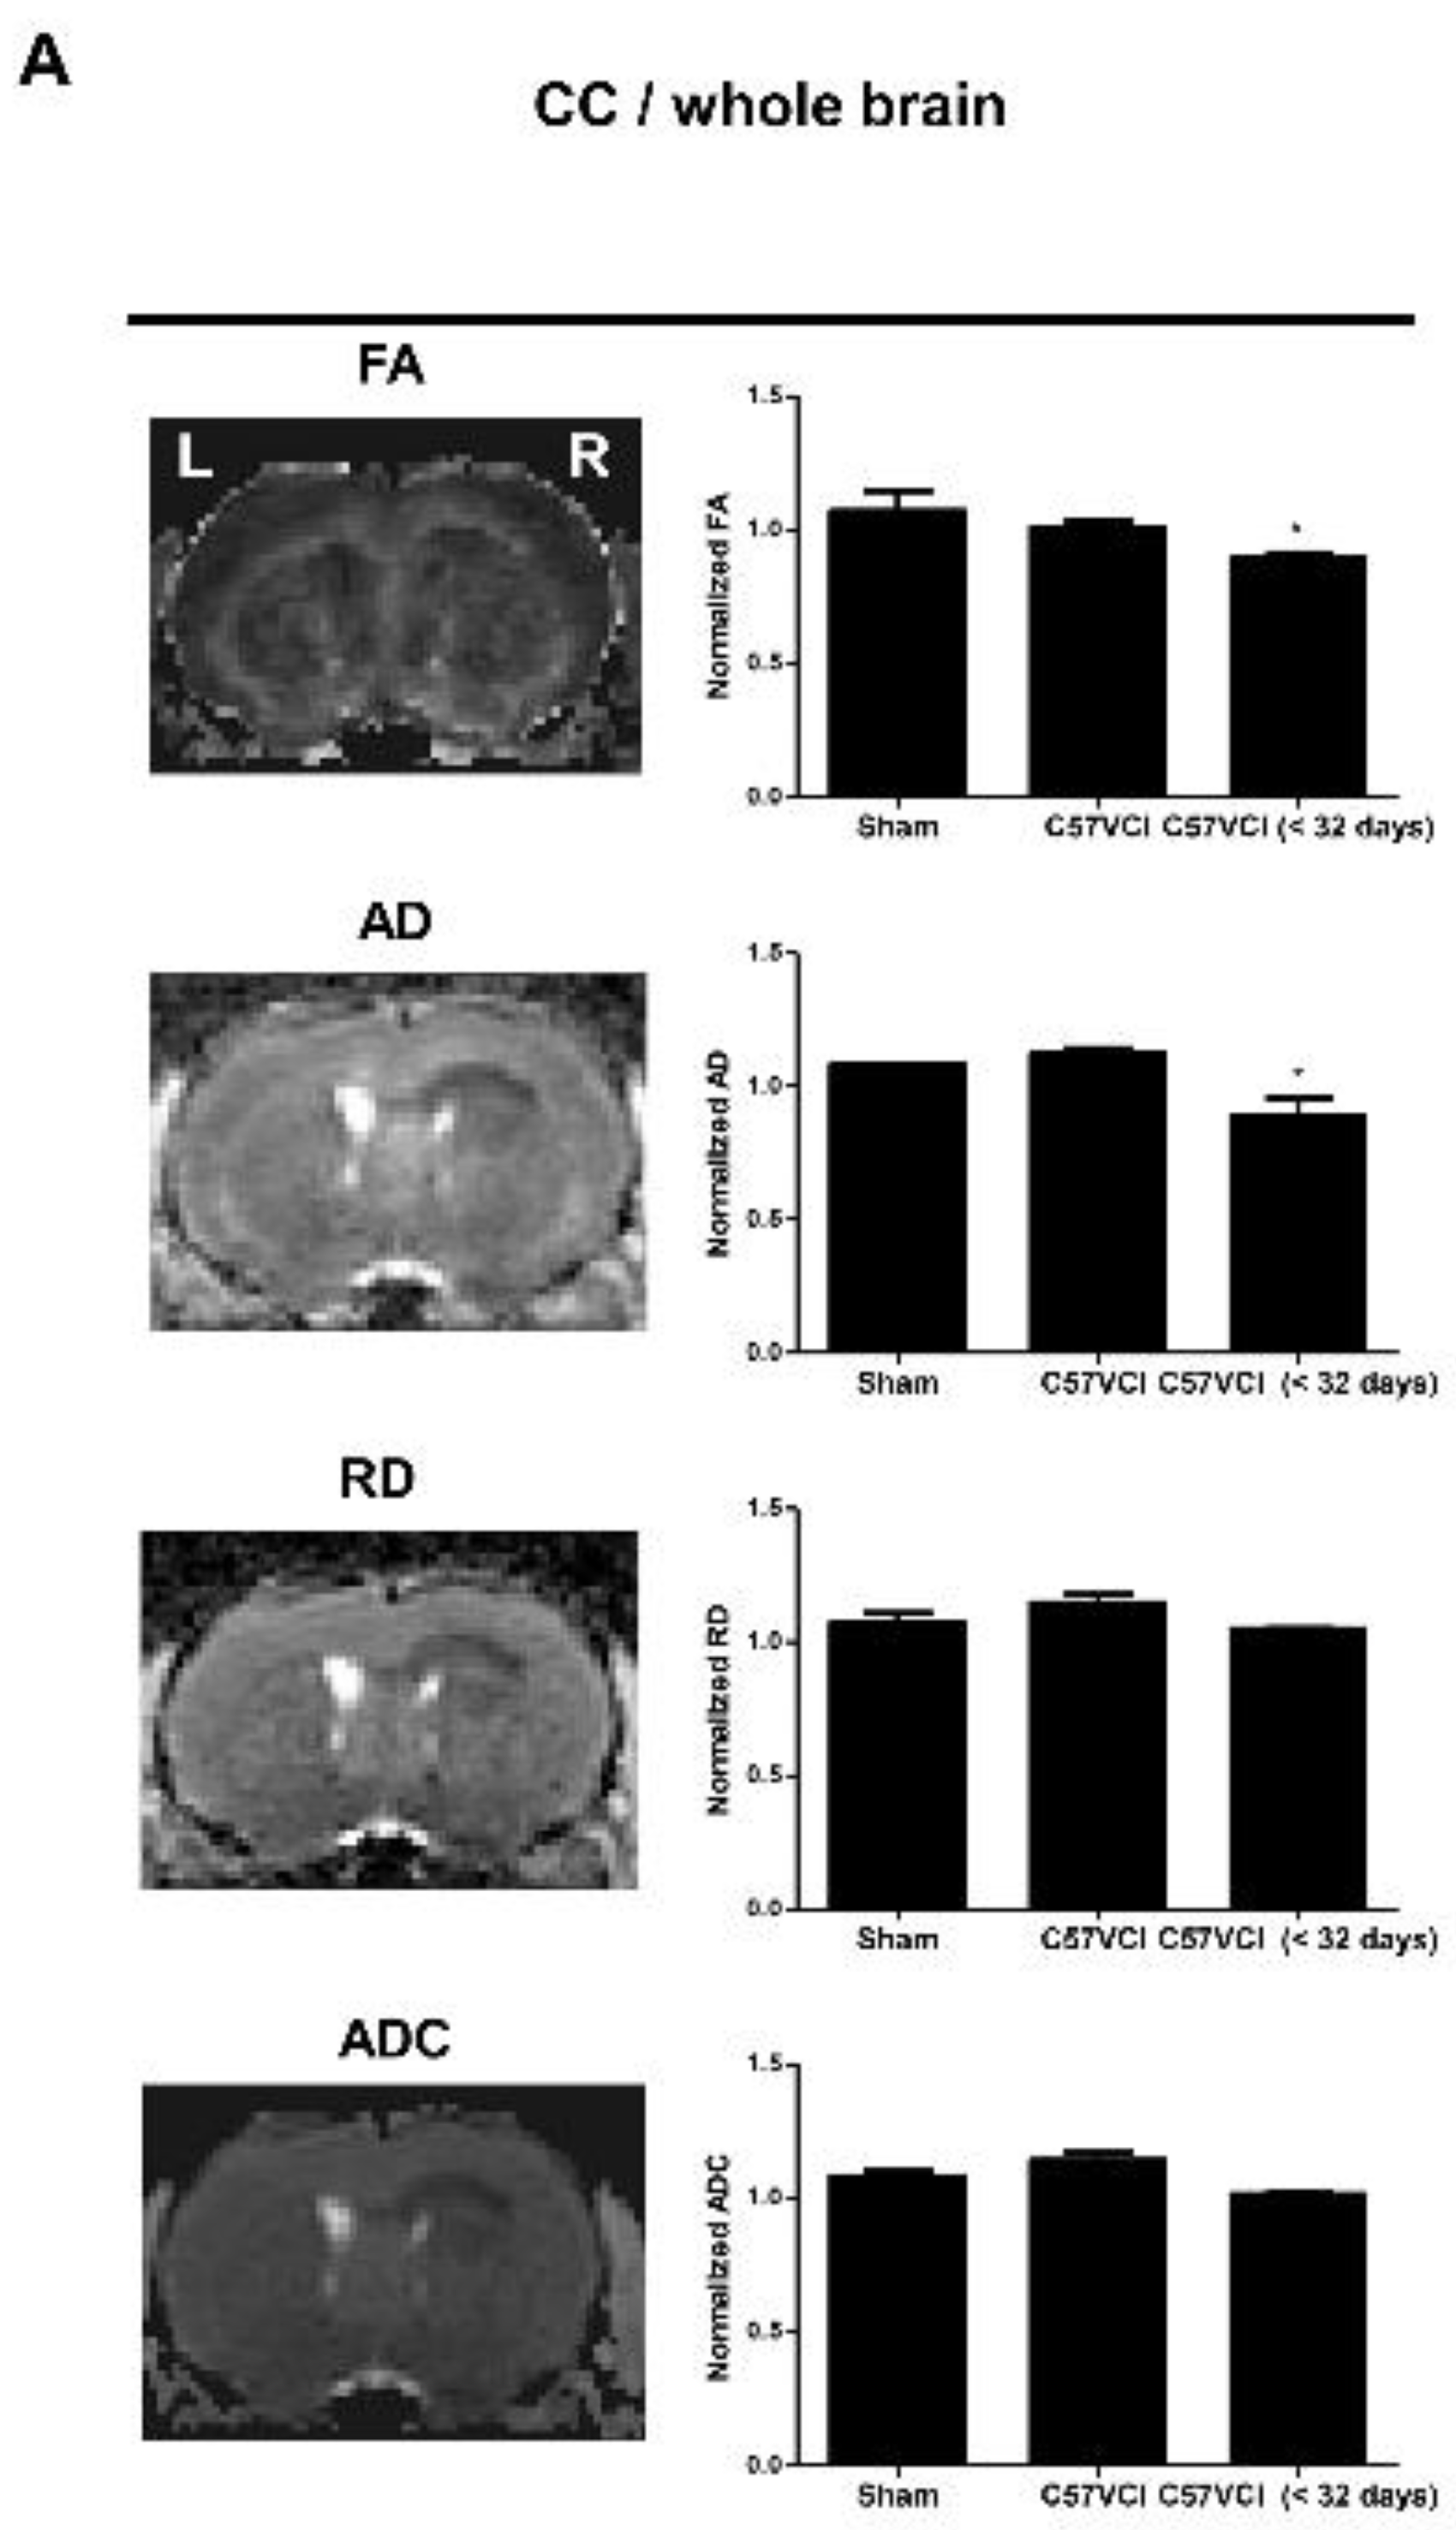

2.4. Differences in DTI Parameters Were Not Significant without the Presence of Infarcts

Interestingly, when comparing the C57VCI (six that survived up to 32 days; C57VCI 1,2,5,6,11, and 12) to the sham group, statistically significant differences in DTI indices (normalized = entire corpus callosum (CC)/whole brain) were not observed (Figure 4A). Although tract density was slightly reduced (normalized: CC/whole brain), the difference was not statistically significant (Figure 4B). We further investigated whether the presence of infarcts in the CC affect DTI parameters (normalized: entire CC including infarct/whole brain).

The effects of VCI on Diffusion Tensor Imaging (DTI) parameters. (A) Tract Density (TD), Axial Diffusivity (AD), Radial Diffusivity (RD), and Apparent Diffusion Coefficient (ADC) maps of the corpus callosum (CC) from a representative animal (far left). The normalized values of the CC (the CC value were divided by the value of the whole brain) were used for group comparisons: Sham, C57VCI (sacrificed at 32 days), and C57VCI <32 days are shown in bar graphs on the right. * p < 0.05 vs. sham; mean ± S.E.M. L indicates left and R indicates the right hemisphere of the mouse brain. (B) Tractography of a representative animal from each of the groups (from left to right: axial, dorsal, left hemisphere, right hemisphere) and the normalized (CC/whole brain) tract density shown as bar graphs. The solid yellow arrows indicate reduced fiber density. (C) Normalized DTI parameters (the value on the side of the infarct was divided by the value of the contralesional side of the C57VCI <32 days group) quantitated by comparing the ipsilesional to the contralesional side of the C57VCI <32 days group. ** p < 0.01, *** p < 0.001 vs. contralesional; mean ± S.E.M.

Three C57VCI mice that died before the 32 days with cerebral infarcts (C57VCI <32 days: C57VCI 15, 16, and 17) were included in the analyses. Compared to the sham group, a statistically significant reduction in FA (* p < 0.05) and AD (* p < 0.05) were observed from the C57VCI <32 days group (Figure 4A). Interestingly, significant changes in demyelination (RD) and tissue integrity (MD) were not observed. When observing the tractography of the corpus callosum, reduced fiber density (yellow solid arrow; Figure 4B) was noted on the ipsilesional side of the C57VCI <32 days group. However, when compared to the tract density of the sham group, differences were not significant. Instead of measuring the DTI indices of the entire corpus callosum, DTI indices of the contralesional side were also compared to that of the ipsilesional side (Figure 4C). Pronounced effects on the DTI parameters were noted when excluding the sham group and comparing the contralesional to the ipsilesional side (Figure 4C). Compared to the contralesional side, a significant reduction in TD (** p < 0.01), AD (*** p < 0.001), RD (*** p < 0.001), and ADC (*** p < 0.001) were noted in the ipsilesional side.